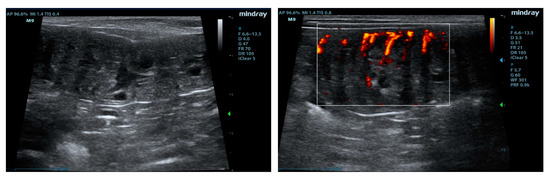

3.1. Ultrasonographic Examinations